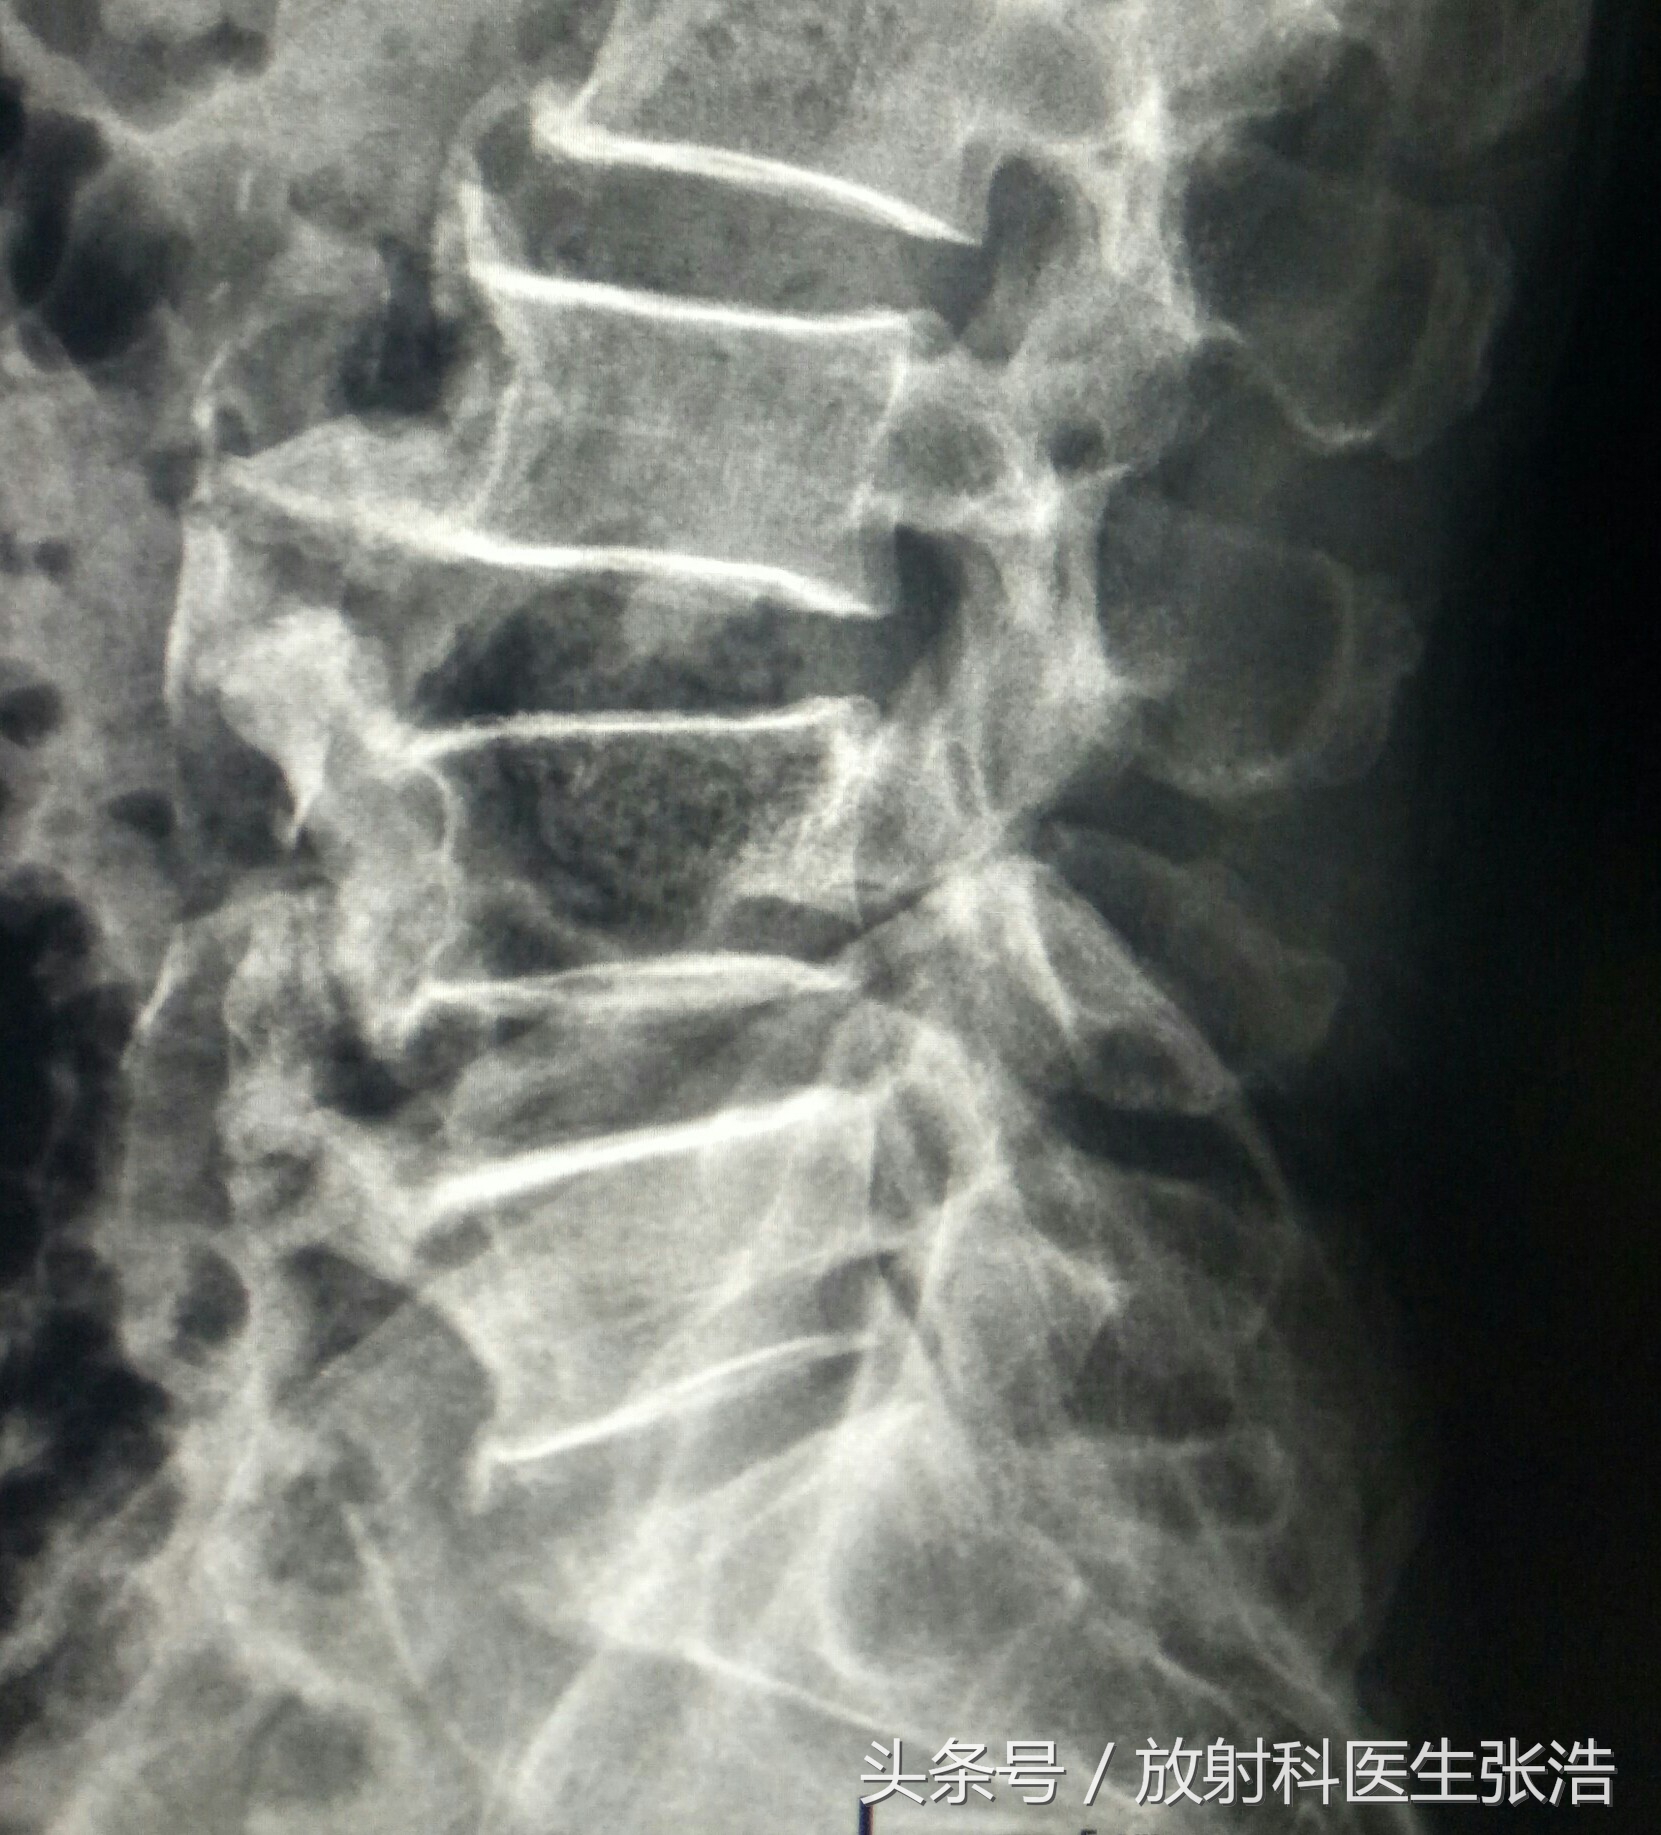

上面这是腰椎和颈椎增生的患者,可以看到椎体缘有明显的骨质增生,因为椎体前后有前纵韧带后后纵韧带,过多的增生往往会影响其活动度,有的增生会压迫到硬膜囊神经根等,所以会造成要背脖子僵硬不适。